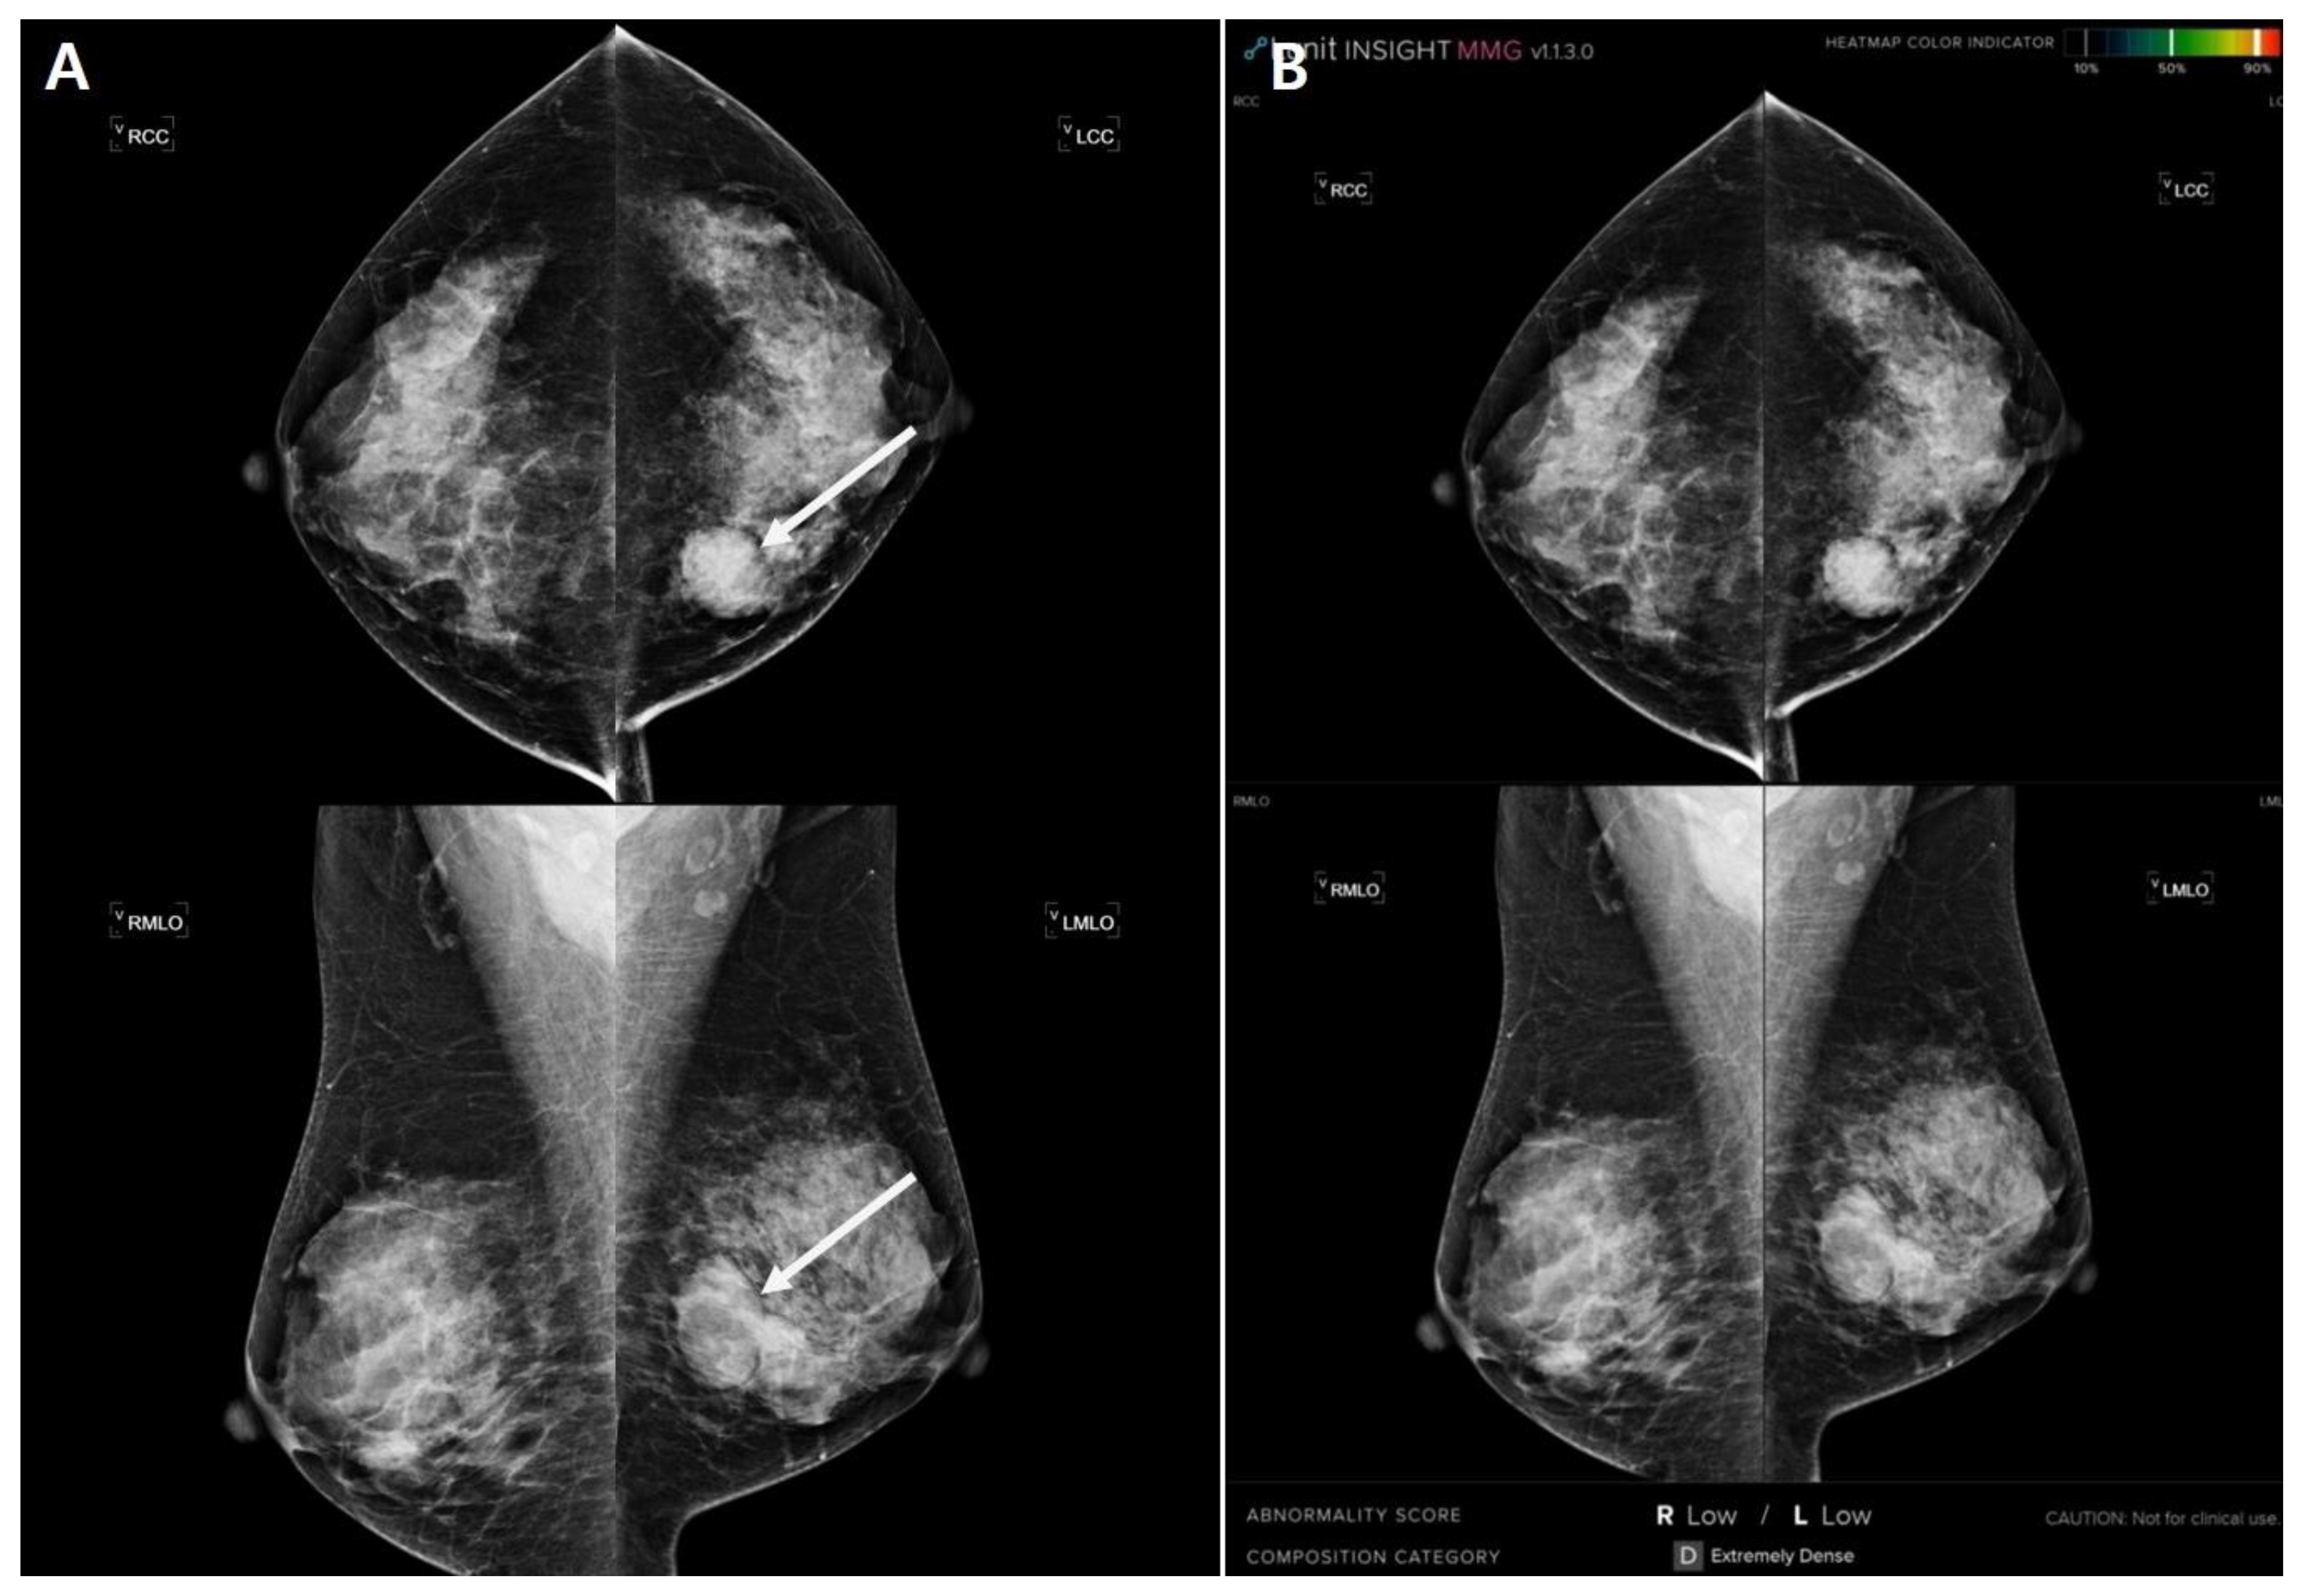

| R1 | 66 | none | c | R | Asymmetry | - | 0.5 | 8.46 | R |

| R2 | 38 | palpation | c | R | Calcification | - | 0.4 | 0.1 | L |

| R3 | 53 | none | b | L | Asymmetry | Existence | 0.4 | 1.3 | L |

| R4 | 53 | palpation | c | L | Mass | - | 3.7 | 0.85 | L |

| R5 | 67 | pain | a | L | Asymmetry | - | 1.6 | 2 | L |

| R6 | 58 | none | c | L | mass | Existence | 0.7 | 7.5 | L |

| R7 | 48 | palpation | c | L | asymmetry | - | 4 | 0.17 | L |

| R8 | 40 | palpation | d | R | asymmetry | - | 3.2 | 0.28 | R |

| R9 | 44 | none | d | R | distortion | - | 1.5 | 0.01 | R |

| R10 | 45 | none | d | R | calcification | - | 1.6 | 6.53 | R |

| R11 | 47 | none | d | R | calcification | Existence | 0.5 | 1.92 | L |

| R12 | 45 | palpation | d | R | mass | - | 1.5 | 0.15 | R |

| R13 | 51 | none | c | R | calcification | - | 0.5 | 3.5 | R |

| R14 | 66 | none | a | R | mass | Existence | 0.6 | 0.01 | L |

| R15 | 59 | none | b | L | other | Existence | 2.7 | 0.83 | L |

| R16 | 66 | discharge | c | L | asymmetry | Existence | 0.7 | 3.5 | L |

| R17 | 42 | none | b | L | mass | - | 1 | 0.68 | L |

| R18 | 67 | none | b | R | asymmetry | - | 0.7 | 0.21 | R |

| R19 | 46 | palpation | c | L | mass | - | 1.5 | 1.03 | L |

| R20 | 56 | none | c | L | mass | Existence | 0.8 | 2.53 | R |

| R21 | 70 | none | c | L | distortion | Existence | 1 | 5.27 | L |

| R22 | 50 | palpation | c | R | asymmetry | Existence | 1 | 0.13 | R |

| R23 | 47 | none | d | L | calcification | - | 0.5 | 6.29 | L |

| R24 | 78 | none | c | R | asymmetry | Existence | 1 | 0.08 | R |

| R25 | 46 | none | c | L | distortion | Existence | 0.8 | 8.72 | L |

| R26 | 68 | palpation | b | L | distortion | Existence | 1.5 | 7.06 | L |

| R27 | 59 | none | c | R | asymmetry | Existence | 1.4 | 0.34 | L |